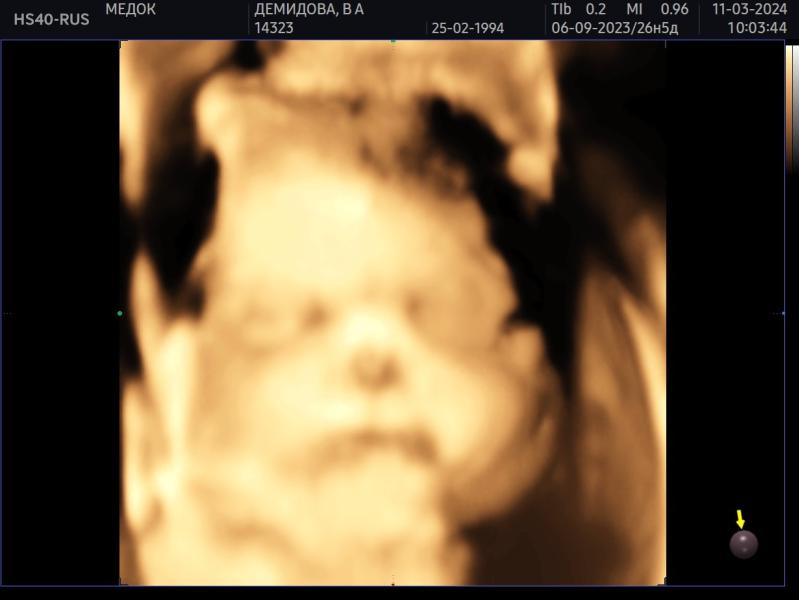

Была сегодня на 3д/4д узи в своей клинике, где веду беременность - Медок Марфино. Узист Лункина ЕГ (вдруг кто тоже туда планирует идти).

Проходила у нее два скрининга, будет у нее же третий, и вот сегодня промежуточное узи.

Срок 27.5 по 1 скринингу, так и опережаем месячные на неделю.

Сын весит около 1163 г. Ваши детки сколько весили на таком сроке?

Врач говорит что хороший вес для этого срока.

В целом все в порядке, лоханки так и остались слегка расширены, но врач сказала это не страшно. ...